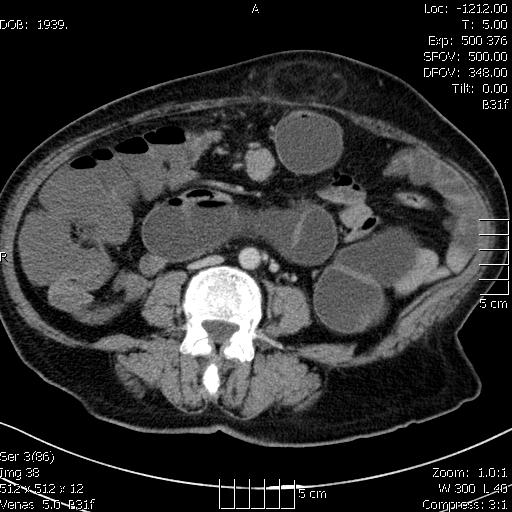

Megnagyobbodott, intenzíven halmozó mesenterialis nyirokcsomó a középvonalban

A vastagbelek vízzel töltve (hydro-colo CT készült, mert a colonoscopia nem volt végig kivitelezhető)